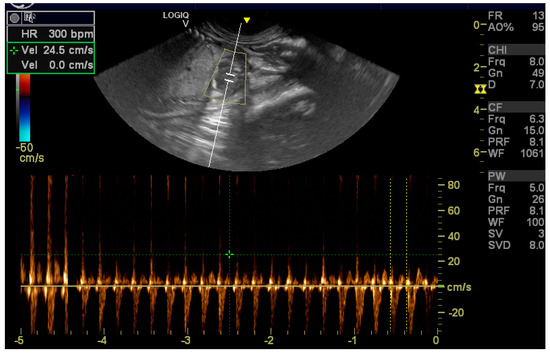

Ultrasound, Histomorphologic, and Immunohistochemical Analysis of a Cardiac Tumor with Increased Purkinje Cells Detected in a Canine Fetus 42 Days into Pregnancy

2. Case Description

2.1. Clinical Findings